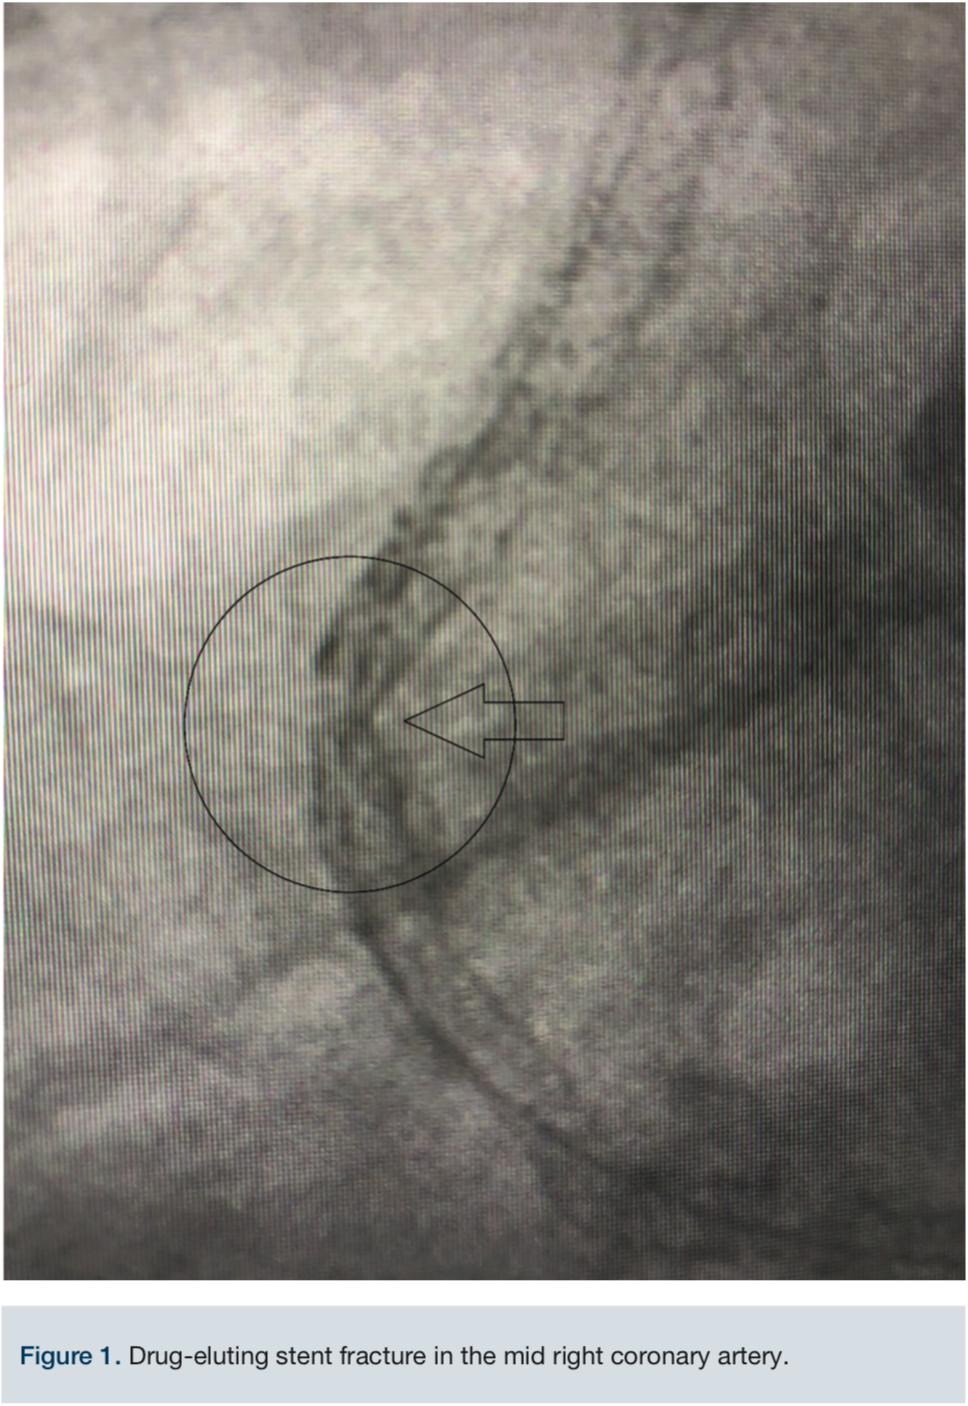

Access was obtained via the right common femoral artery. The initial lesion in the mid proximal RCA can be seen in Figure 2. An 8 French (Fr) long Destination sheath (Terumo) was used for maximum support, and a 0.75 Amplatz left (AL) 2 Guide catheter (Boston Scientific) was used for access support and assistance. A Balance Middleweight (BMW) wire (Abbott Vascular) was initially used to advance the catheter into the target artery. We switched to a 300 cm PT choice wire (Boston Scientific) in an attempt to cross the existing stent lumen, with the use of a 6 Fr Guideliner (Teleflex) for additional support. A 2.5 mm x 12 mm balloon (Medtronic) failed to cross the mid RCA stent fracture and ISR. The two markers on the balloon created a too-large catheter diameter, so a 1.25 mm x 12 mm single marker balloon (Medtronic) was chosen instead and successfully crossed. The balloon was inflated to 20 atmospheres (atm) and removed. A second attempt to pass the original 2.5 mm x 12 mm balloon (Medtronic) once again failed. The ELCA catheter was positioned just proximal to the mid RCA ISR within the fractured stent lumen. We started with an 0.9 laser catheter with the tip terminating just proximal to the ISR. An initial fluence of 45 mJ/mm2 was applied and gradually increased to a fluence of 80 mJ/mm2 for a total of almost 5 minutes while the tip was still positioned proximally to the ISR. The laser then was able to advance through the obstruction and was removed. Over the wire, a 2.5 mm x 12 mm balloon was inflated up to 20 atm for 25 seconds and then replaced with a 3.0 mm x 20 mm balloon (Medtronic) inflated to nominal pressure. The same 3.0 mm balloon was used at the very proximal aspect of the ISR as a pre-dilation before two drug-eluting stents (DES) were placed: a 3.0 mm x 18 mm Onyx DES (Medtronic) at the mid RCA and a second 3.0 mm x 30 mm Onyx DES at the proximal to mid RCA. The 3.0 mm x 18 mm Onyx DES stent was deployed at 22 atm for 15 seconds and the 3.0 mm x 30 mm Onyx DES was deployed 20 atm for 10 seconds. Post stent deployment, angiography clearly demonstrated reduction of the stenosis from approximately 99% to <10% at the site of the original stenosis in the proximal to mid RCA. At the end of the procedure, Thrombolysis In Myocardial Infarction (TIMI)-III flow was achieved (Figure 3). Inline flow was successfully restored across the entire RCA. The procedure was uncomplicated, but required the use of significant amounts of contrast (500 mL) and fluoroscopy (81.1 minutes). The patient was discharged the following day without incident, and has thus far remained asymptomatic throughout his follow-up with his referring cardiologist.